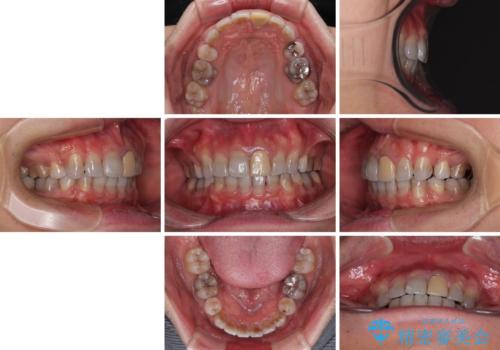

- 口元の突出感を改善するための抜歯矯正を終えた患者様ですが、幼少期からの変色した歯をセラミッククラウンにて自然な色合いに変えていくこととしました。

口を開けたときに目につく範囲を希望されたため上下ともに8本ずつをオールセラミッククラウンによる補綴治療を行うこととしました。

近年では大変珍しいですが、胎児あるいは乳幼児期の抗生物質の影響で永久歯が変色してしまうことがあります。

ホワイトニングでの改善は期待できないため、オールセラミッククラウンによる補綴治療が必要となります。